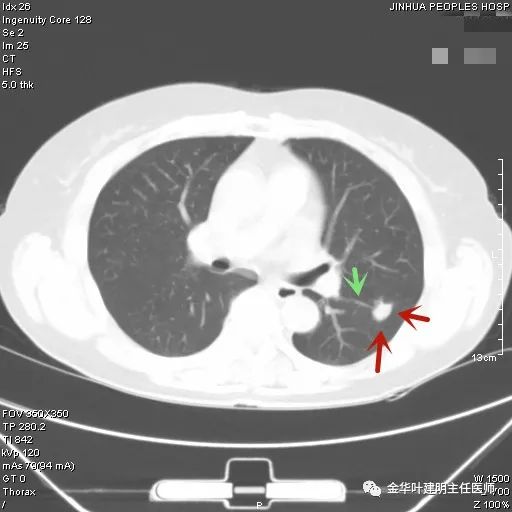

上图示慢性炎结节。我们见其桔色箭头示长毛刺征,绿色箭头示有血管贴边,但进出病灶的血管粗细相对没有什么改变(说明没有被病灶窃取多少血供),整体病灶边缘偏模糊。